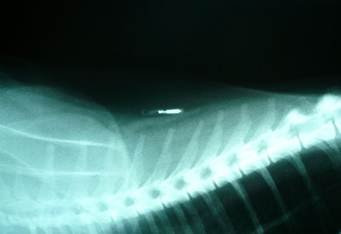

There was no hesitation then 13 years ago for my new border collie pup ‘Star’ to be micro-chipped by the breeder using this wonderful new modern technology. A clever little chip about the size of a large grain of rice, holding a number unique to Star and registering it with my name address and contact details. All I needed to do was contact the database service and notify them she was lost and eventually, all being well, they would trace either Star to me or vice versa and we would be reunited.

Unfortunately, due to the site of the chip – in the scruff at the back of her neck – the chip eventually migrated and ended up somewhere in the ruffle low at the front of her chest. Needless to say I wasn’t impressed and felt most irritated.

Truth: It is imperative the chips are implanted by a trained and certificated implanter in the right location on your cat. To be fair, when this was reasonably new technology it wasn’t common knowledge that chips could eventually migrate. Lessons were rapidly learned and implant technique adjusted, along with the upgrade of chip technology.

Manufacturers now design the chips with anti-migrating properties. This gives the body time to allow the natural process for some connective tissue to form around the chip. When they’re implanted properly, today’s chips won’t migrate.